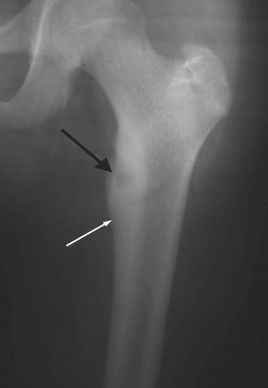

骨樣骨瘤是一種成骨性良性腫瘤,多見于兒童和青少年,好發(fā)于下肢長骨。其臨床特征是患部疼痛,阿司匹林可止痛。病理特征是有一個小而圓的骨組織核心,由骨樣組織和不成熟骨小梁組成,周圍為硬化骨。X線顯示骨干增粗致密,其中有一約1cm直徑X線透亮區(qū),中央有一小致密影,周圍為硬化帶。將腫瘤核心的“巢穴”及周圍硬化骨予以切除即可治愈。